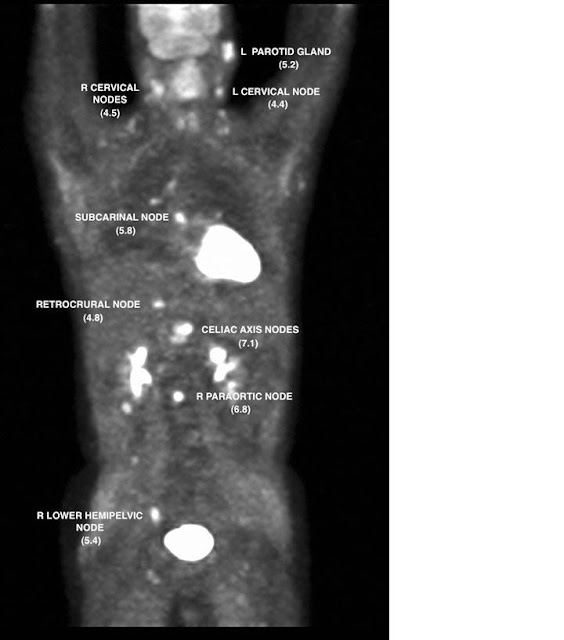

Case of Non Hodgkin's lymphoma Download Scientific Diagram Case Study Non Hodgkin S Lymphoma Lymphomas are solid tumors of the immune system and include 14% of all head and neck malignancies. Hematologic malignancies, a panel of experts identified clinical challenges in managing patients with lymphoma. At the nccn 2019 annual congress: although some lymphomas require minimal intervention for cure or remission, others can be difficult to treat and are associated with poor patient. Case Study Non Hodgkin S Lymphoma.